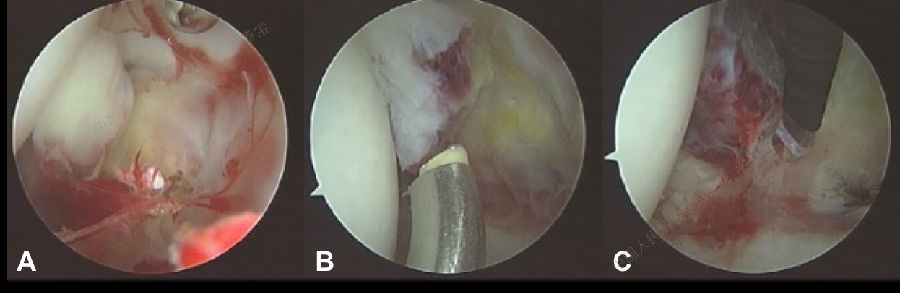

3. 髋臼或股骨头软骨损伤

此种损伤多发生于跌倒时,直接暴力作用于大粗隆,使外力直接传导至髋关节,青壮年由于骨质致密,容易造成软骨损伤,老年人发生股骨颈骨折,儿童则易伤及骨骺。单纯体检难以诊断软骨损伤,MRI显示关节腔积液、软骨下骨水肿,间接提示软骨损伤的可能。传统开放手术早期感染、粘连、软组织挛缩、深静脉血栓形成、肺栓塞、异位骨化和神经肌肉功能障碍等的危险性较高,且康复时间较长。治疗:关节镜下微创手术可通过刨削刀和射频对损伤软骨进行修整,及时清理和取出游离或不稳定的软骨,能够明显缓解症状,大大降低了手术的危险性及并发症,手术效果满意。